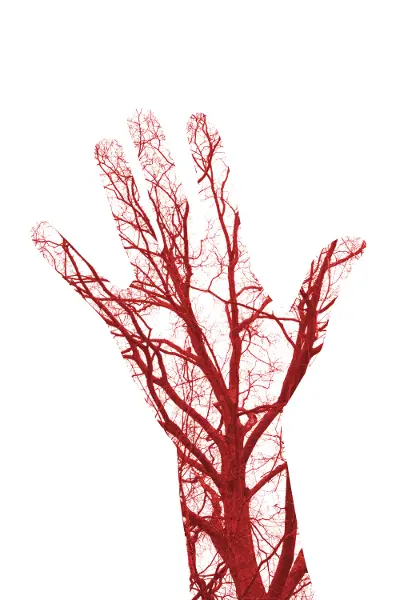

A complementary mechanism of action may be in how ginger affects circulation: As an effective stimulator of peripheral circulation, ginger may help in alleviating cramping pain.[8] This ties into our TCM theory whereby Stagnation or Stasis of Blood results in a deep stabbing, throbbing pain; Therefore symptoms may be alleviated with improved circulation, also described in TCM as “smooth flow of Blood and Qi”, most notably as Liver Qi and Liver Blood which affect menstrual flow.